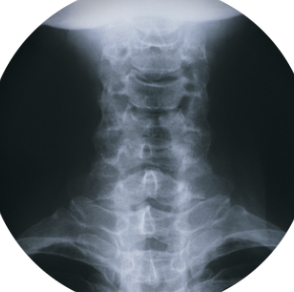

목 디스크에 좋은 운동에 대해 알아보도록 하겠습니다. 목 디스크는 목이나 어깨에 통증을 유발하는 흔한 질환입니다. 목 디스크는 척추의 쿠션 역할을 하는 디스크가 손상되거나 탈출하여 신경을 압박하는 것을 말합니다. 목 디스크의 원인은 다양하지만, 자세나 습관이 중요한 역할을 합니다. 잘못된 자세로 오랫동안 앉아있거나, 스마트폰이나 컴퓨터를 사용하면서 목을 구부리거나, 무거운 물건을 들거나, 근육을 과도하게 사용하는 등의 행동은 목 디스크의 위험을 높일 수 있습니다.

목 디스크는 목 뒤의 척추와 척추 사이에 있는 디스크라는 고무질 물질이 손상되거나 탈출하여 신경을 압박하는 질환입니다. 목 디스크의 증상은 목 통증, 팔 저림, 근육 약화, 마비 등이 있습니다. 목 디스크의 치료 방법은 증상의 심각도와 개인의 상황에 따라 다릅니다. 일반적으로 비수술적 치료로 통증을 완화하고 디스크를 회복할 수 있습니다. 비수술적 치료에는 휴식, 약물치료, 물리치료, 침술요법 등이 있습니다. 만약 비수술적 치료가 효과가 없거나 증상이 심한 경우에는 수술을 고려할 수 있습니다. 목 디스크를 예방하고 관리하기 위해서는 올바른 자세를 유지하고, 목 주변의 근력을 강화하고, 스트레칭을 꾸준히 하는 것이 중요합니다.